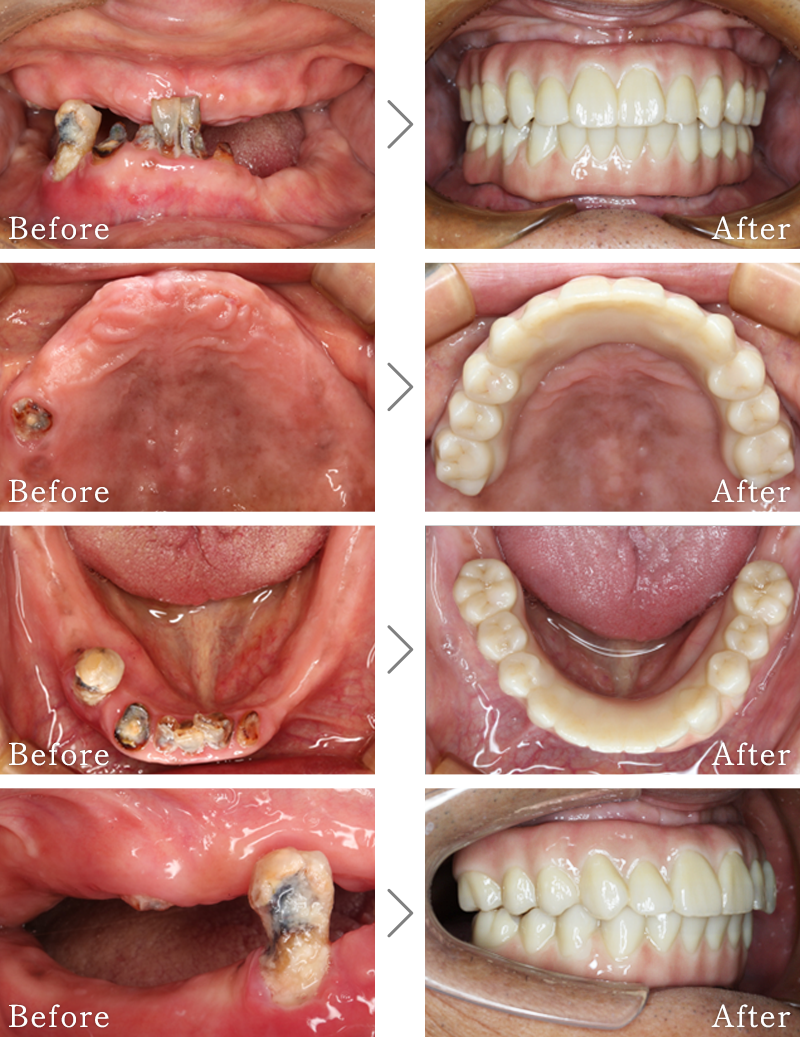

CASE5

主訴 前歯がグラグラして噛めないのと抜けそうで心配。

治療法 抜歯した後、歯周病で溶けて無くなってしまった骨を再生する手術とインプラント手術を同時に行なっています。

治療期間 8ヶ月

費用 CT:16,500円(税込)

+ インプラント治療:525,800円(税込)

+ 造骨処置:88,000円(税込)

合計:630,300円(税込)

CASE6

主訴 入れ歯が合わず、痛くて噛めない。食事ができない。

治療法 入れ歯を新しく作成し、噛み合わせなどの確認をしたのち、左右2本ずつインプラントを使用して噛める状態に回復させています。

治療期間 5ヶ月

+ 静脈内鎮静法:77,000円(税込)

+ インプラント治療:2,321,000円(税込)

合計:2,414,500円(税込)